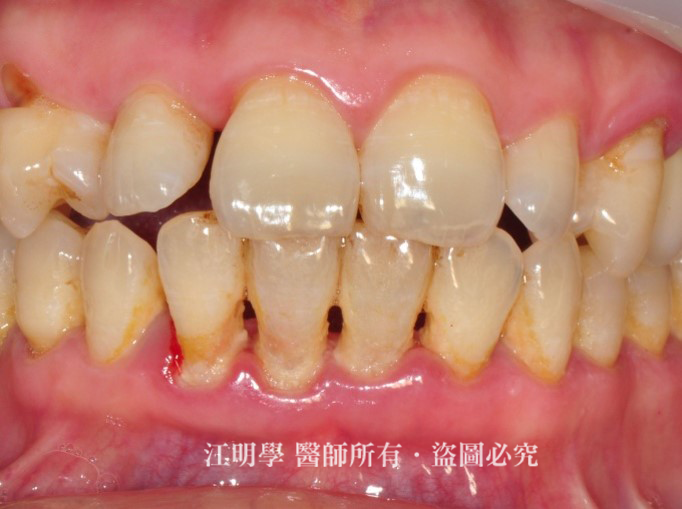

61歲的劉先生,因平時口腔清潔不當,造成牙結石堆積、牙齦紅腫萎縮,且刷牙時會出血。因為缺牙影響日常飲食,因此前來求診。

經江醫師診斷,劉先生的口腔有嚴重牙周病,需先進行牙周病治療,待牙周恢復健康後再安排植牙療程。 考慮到劉先生年紀已大,恢復力較差,建議採用微創水雷射治療取代傳統需動刀的牙周手術療程,與傷口較小的微創植牙。

治療前:植牙將缺牙補齊,重建口腔咬合。